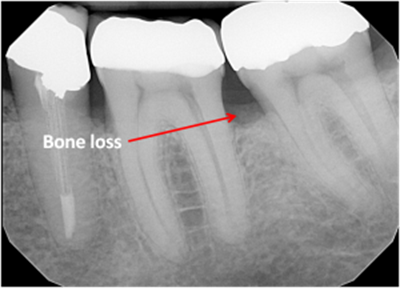

Digital x-rays can be used to diagnose:

- Bone loss